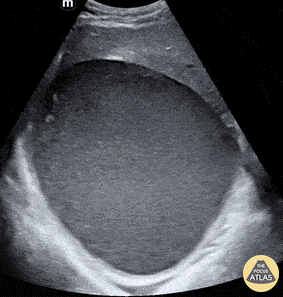

66 y/o male with a history of a recent CBD stent placement complicated by a ruptured hepatic artery resulting in a subcapsular liver hematoma that required IR drainage. He now presents to the ED with progressively worsening right upper quadrant abdominal pain. POCUS was instrumental in monitoring for continued bleeding following the initial drainage. In the clip, you can see the large hematoma, measuring 15 x 13 cm, obscuring most of the liver. Patient was admitted for surgical deroofing. Jennifer Kaminsky, MD PGY-2; @jen_kaminskyMD Pamela Santivanez, MD PGY-1 Sean Beckman, Rocky Vista University COM OMS-4 Joshua Greenstein, MD, Director of ED Ultrasound Northwell Health – Staten Island University Hospital